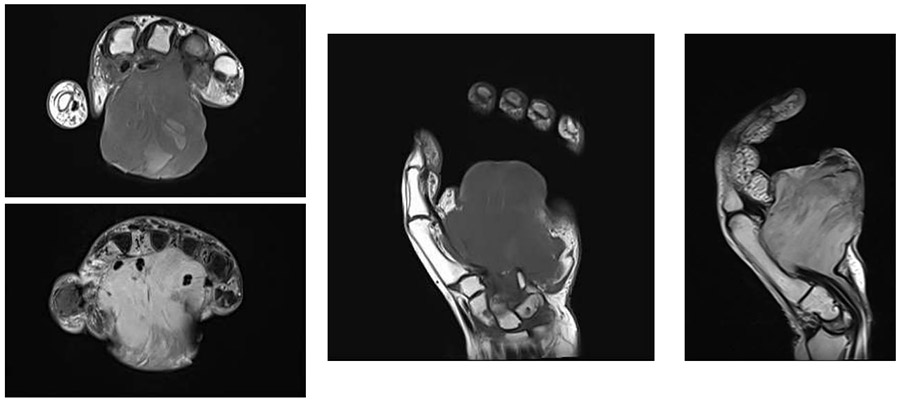

Ameliyat Öncesi: MR’da el volar yerleşimli düzensiz sınırlı, yaygın tutulum gösteren heterojen kitle görülmekte